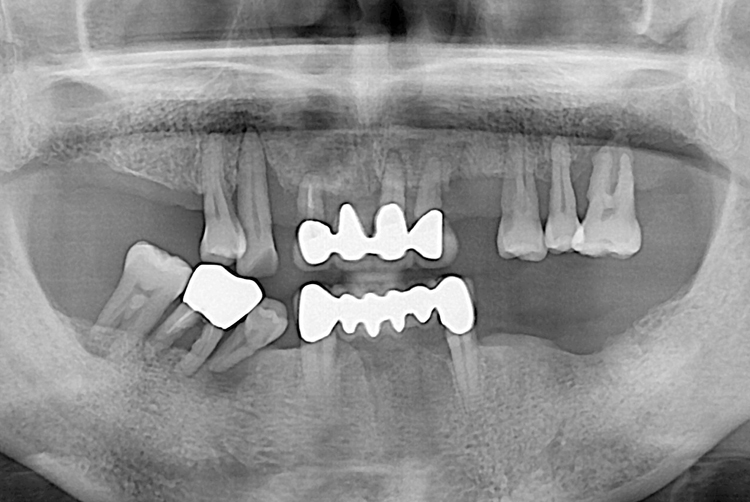

[임플란트] 임플란트

치료전 : 2019-04-25

1497 윤종길_후.jpg

치료후 : 2019-06-27

세종치과는 많은 환자와 다양한 케이스를 바탕으로 항상 편안한 임플란트 수술을 제공하고자 노력하고,

오래동안 튼튼히 쓸 수 있는 임플란트 수술을 가장 큰 목표로 삼고 있습니다